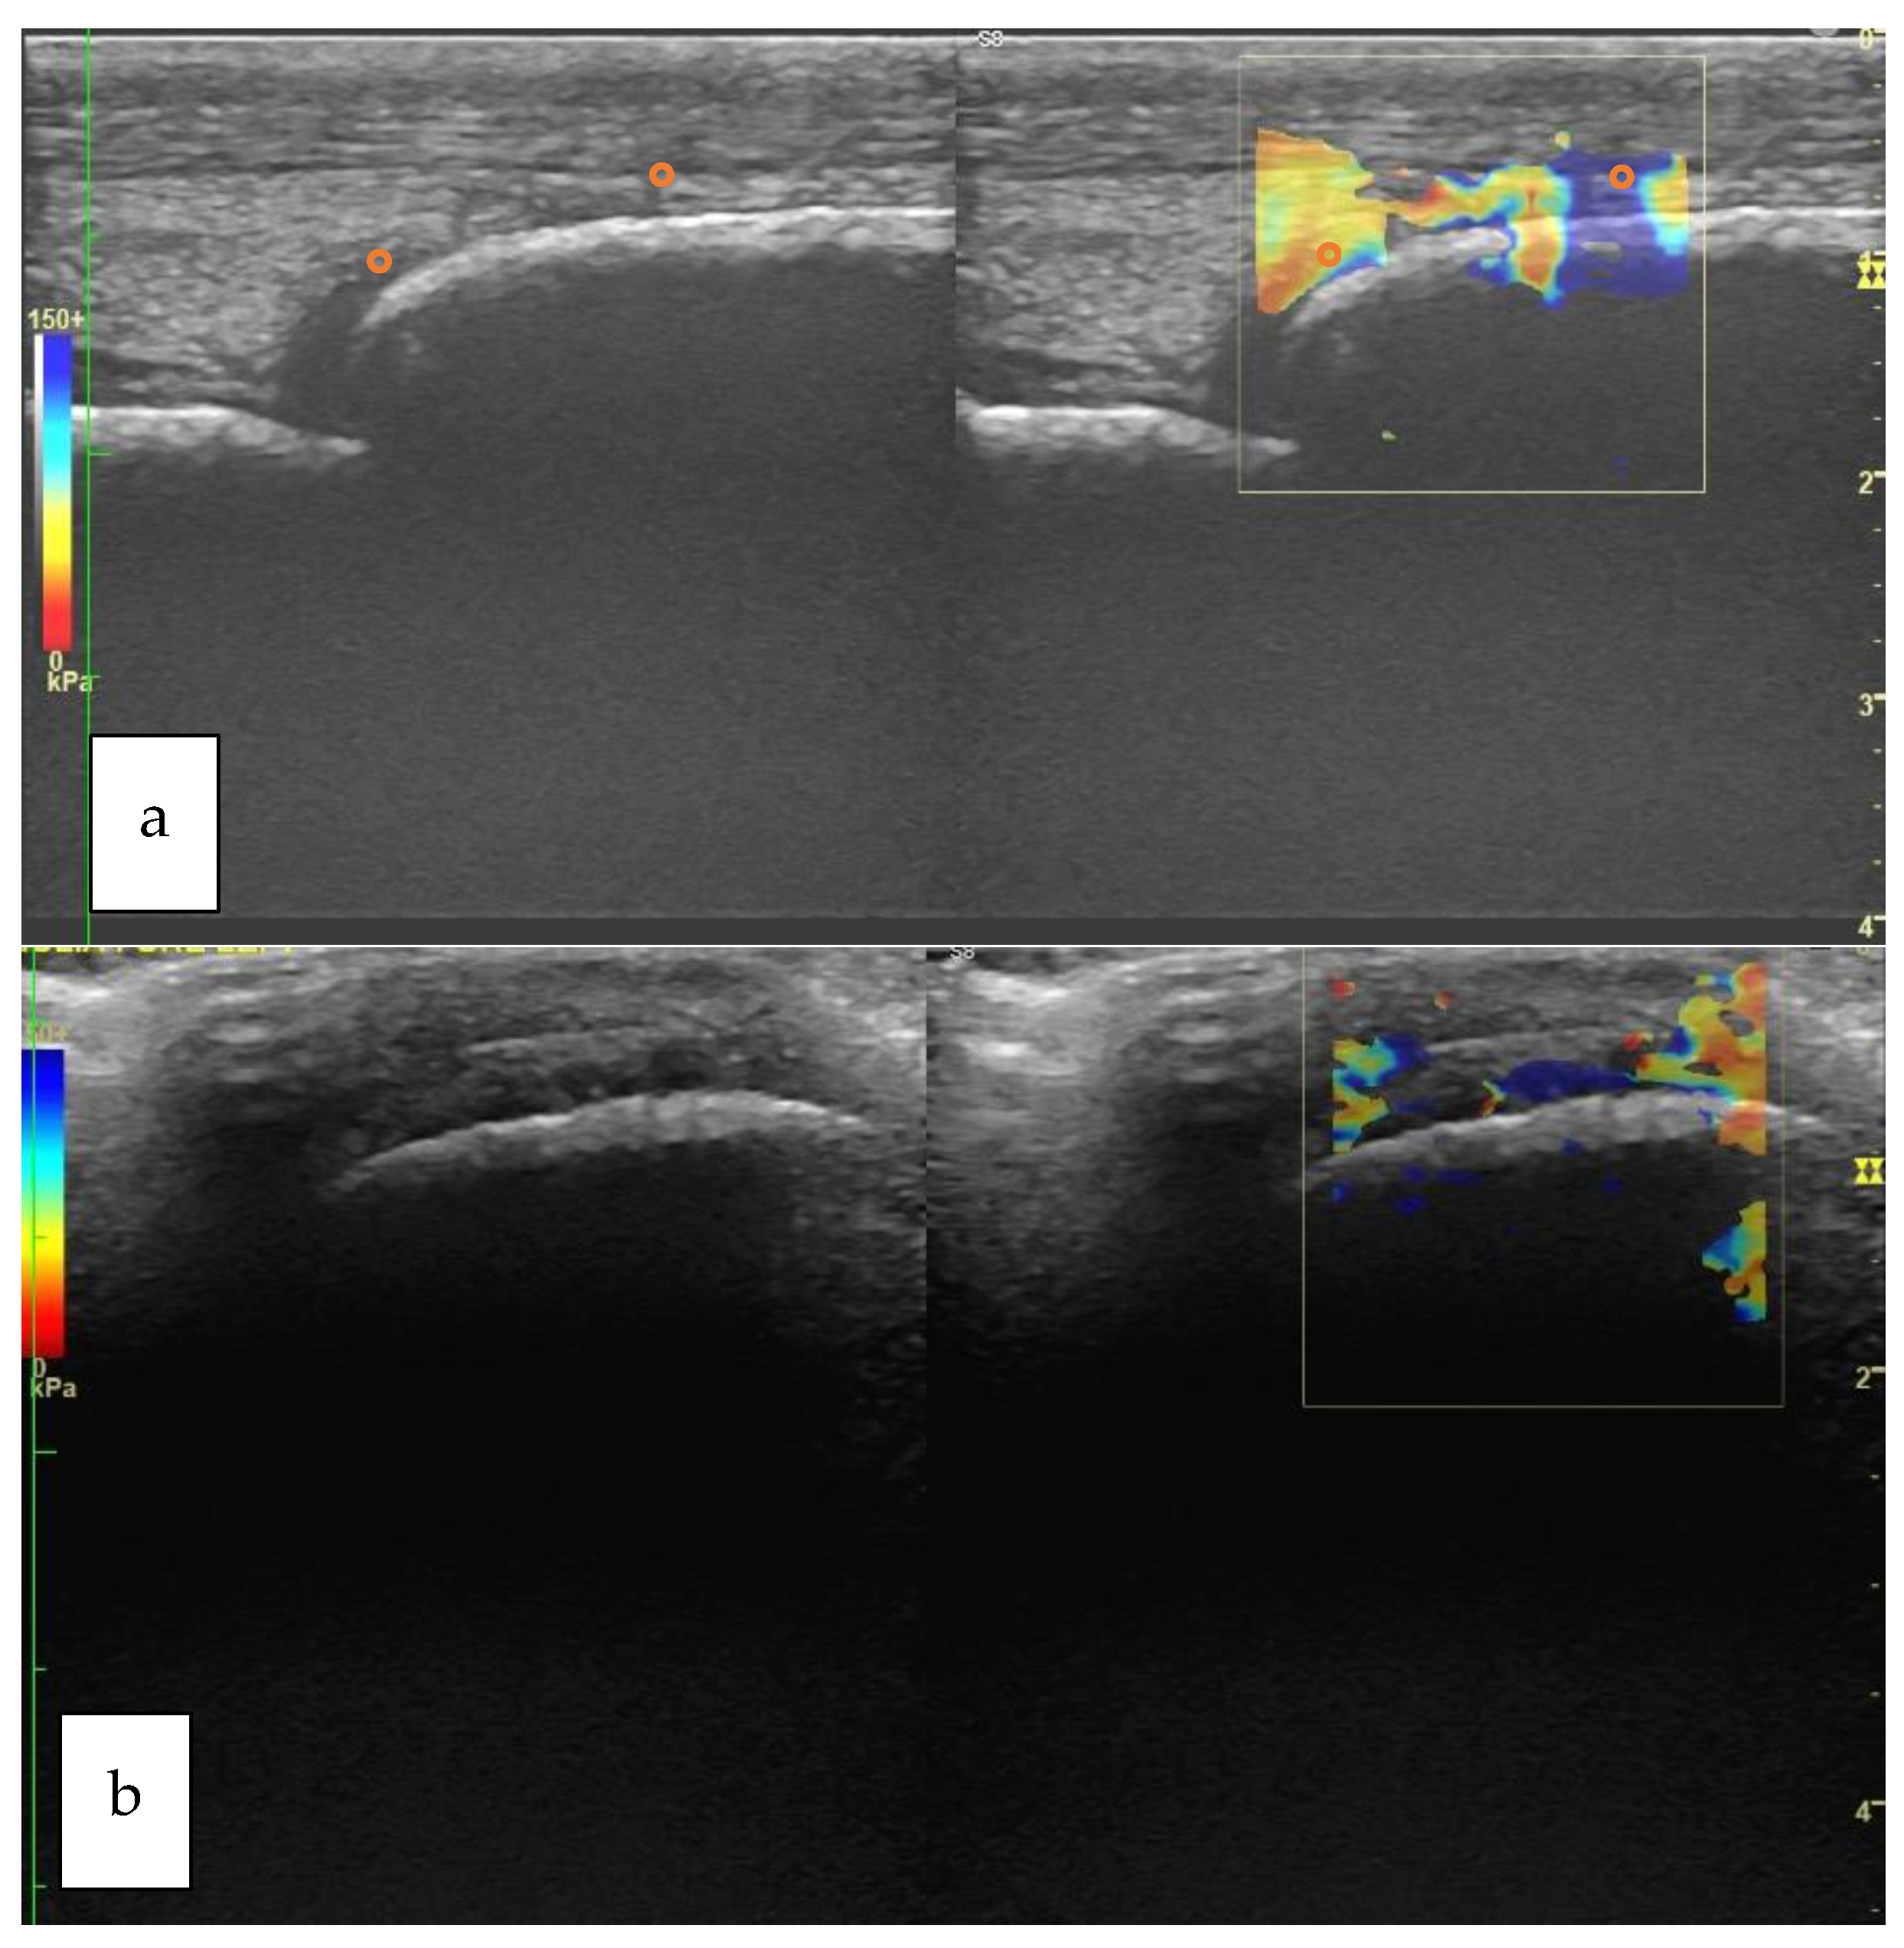

Typical longitudinal and transverse elastograms are shown in Figure 3 for Group H and in Figure 4 for Group P.

Figure 3. Longitudinal (a) and transverse (b) view of the metacarpophalangeal joint of a horse belonging to Group H. The orange circle that is superimposed to the elastogram shows the positioning of the ROI. The B-mode corresponding to each elastogram is shown on the left of each box (Group H: horses not affected by osteoarthritis; ROI: Region of Interest).